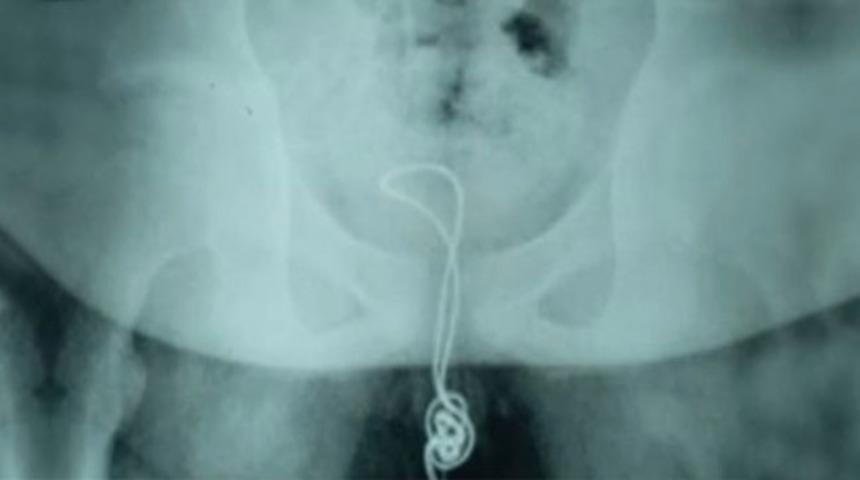

Adı açıklanmayan Çinli çocuk, cinsel organından içeri soktuğu kablonun mesanesinin içinde düğüm olması üzerine geri çıkaramadı. Yaklaşık 20 santimetrelik kablo yüzünden dayanılmaz derecede acı çeken çocuk, durumu ailesine söylemek zorunda kaldı.

Çin'in kuzey-doğu Heilongjiang eyaletindeki Linkou şehrindeki bir hastaneye kaldırılan çocuğun içinde düğümlenen kabloyu doktorlar da dışarı çıkarmayı başaramayınca tek çare olarak ameliyata alındı ve kablo mesanesinden çıkarıldı.